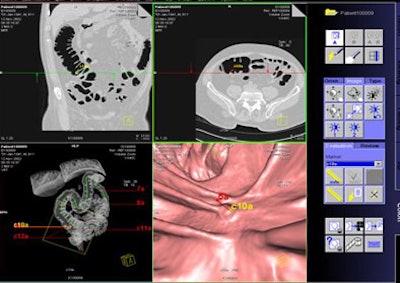

The study by Graser, Dr. Christoph Becker, Dr. Maximilian Reiser, and colleagues tested the performance of a virtual colonoscopy CAD system (syngo Colonography CT with Polyp-Enhanced View [PEV], Siemens Medical Solutions, Erlangen, Germany) that was investigational at the time of the study but has since been approved by the U.S. Food and Drug Administration for clinical use, Graser said.

![]() |

| The syngo Colonography CT CAD interface. All images courtesy of Dr. Anno Graser. |

Axial slices 1-mm thick were reconstructed for 3D visualization. Two expert readers interpreted the data using a primary 3D endoluminal approach. The CAD system was used as a second reader to assess its sensitivity for detecting polyps, as well as the number of false-positive findings per dataset.

The reconstructed images were read on a 3D Siemens syngo Colon postprocessing workstation by an expert reader with experience in reading more than 700 virtual colonoscopy cases.